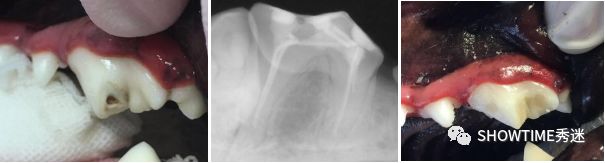

犬齿的根管治疗手术前后

臼齿的根管治疗手术前后